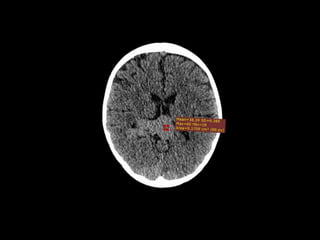

TC SIMPLE DE CRANEO

08/06/2023

CORTE

AXIAL

CORONAL

SAGITAL

VOLUMEN: 25,1 CC

Lesión ocupante de espacio extraaxial

supratentorial a nivel de cisterna cuadrigeminal.

CONCLUSIONES:

TC SIMPLE DECRANEO 08/06/2023

Lesión ocupante deespacio extraaxial supratentorial a nivel de cisterna cuadrigeminal. CONCLUSIONES:

• #18 A NIVEL DE LA CISTERNA CUADRIGEMINAL SE OBSERBA UNA LOE ISOECOICA EN RELACION A ESTRUCTURAS ADYACENTES, QUE TIENE UN COMPORTAMIENTO EXPANSIVO HACIA EL LADO DERECHO, EN EL SIGUIENTE CORTE EVIDENCIAMOS COMO ESTE PROCESO ESTA EJERCIENDO COMPRENSION SOBRE EL ASTA OCCIPITAL DEL VENTRICULO LATERAL DERECHO

• #19 VEMOS COMO SIGUE SU EXPANSION HACIA EL LADO DERECHO Y COMO TAMBIEN COMPROMETE PARCIALMENTE EL ASTA OCCIPITAL IZQUIERDO SIN APRECIAR UNA VENTRICULOMEGALIA, RESTO DEL PARENQUIMA CEREBRAL SIN ALTERACIONES Y ESTRUCTURAS OSEAS CONSERVADAS.